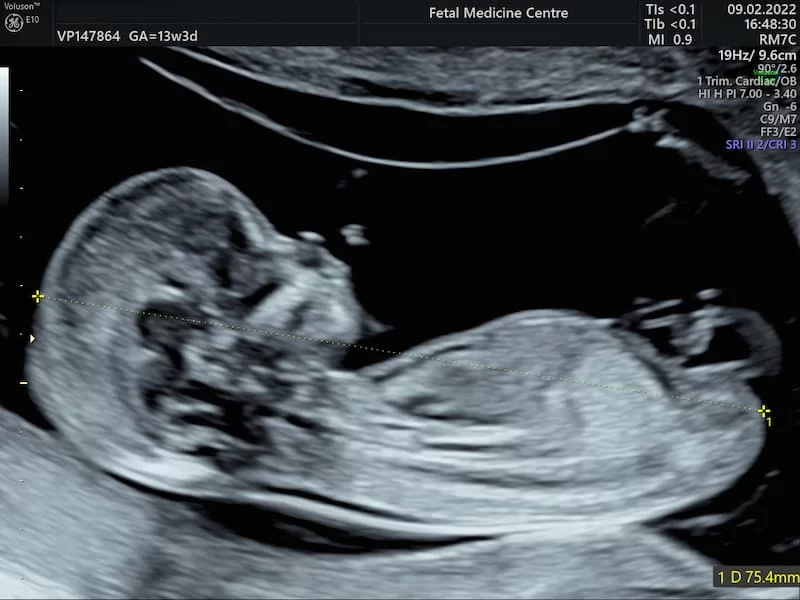

- Ultrason: 14. haftadan itibaren bebeğin cinsiyeti ultrason ile görülebilir. Ancak, kesin sonuçlar genellikle 16. haftadan sonra, özellikle 18-21. haftalarda alınır.

- Bebeğin cinsiyeti ne zaman belli olur? Hamileliğin 16-21. haftaları arasında yapılan ultrason muayenesi ile bebeğin cinsiyeti belirlenebilir. Ancak nadir de olsa yanılmalar yaşanabilir.

- 3 aylık bebeğin cinsiyeti belli olur mu? 3. ay itibarıyla bazı genetik testler ile cinsiyet belirlenebilir. Ancak ultrason ile kesin sonuç almak için genellikle 16. haftayı beklemek gerekir.

- Erkek bebek kaçıncı haftada belli olur? Erkek bebeklerin cinsiyeti genellikle 16-21. haftalarda net olarak belirlenebilir. Ancak bebeğin anne karnındaki pozisyonu bazen net görüntü almayı engelleyebilir.